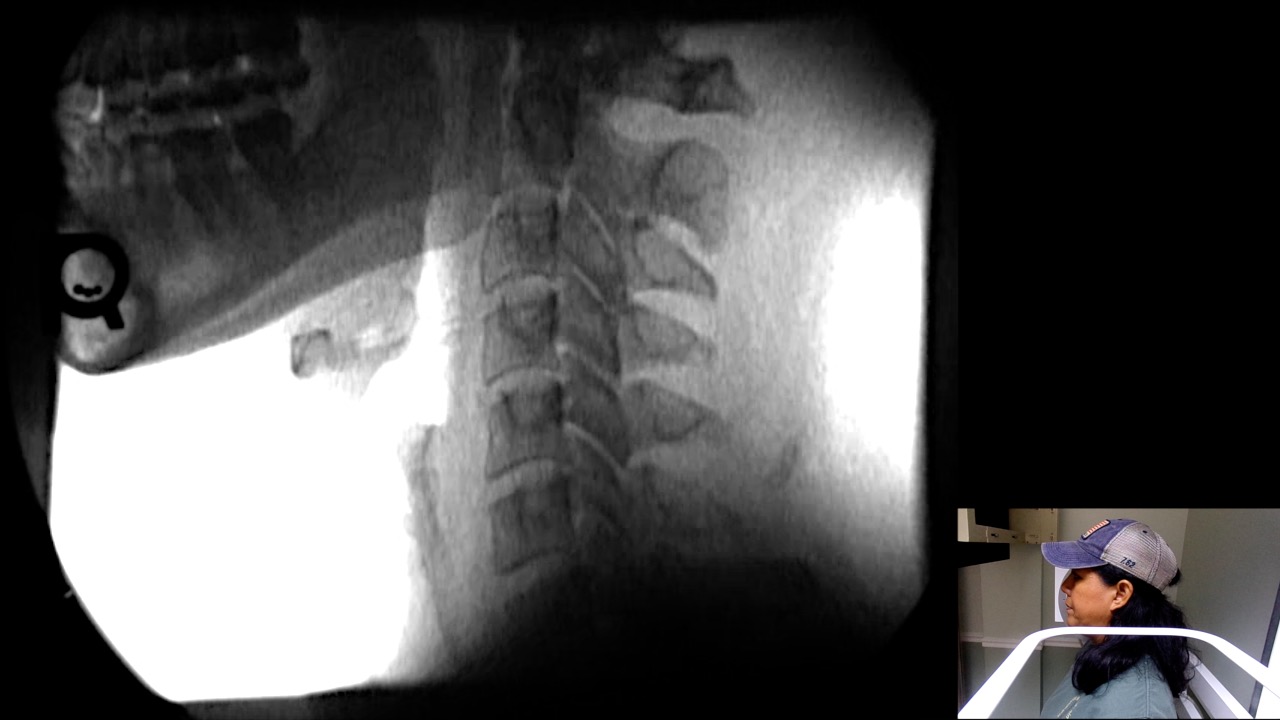

Image Name Image Type Image